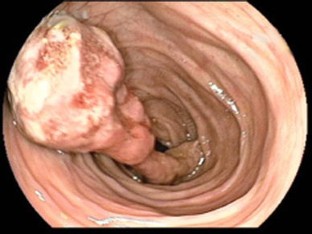

18F-FDG PET/CT in inflammatory pseudotumor of the colon causing intussusception

Inflammatory pseudotumor is a rare benign lesion mimicking malignancy both clinically and radiologically. An accurate diagnosis is still difficult and is based on the histological examination. Since inflammatory pseudotumor is exceptionally rare in the colon, this unexpected lesion can be mistaken for malignancy. We report the first case of inflammatory pseudotumor in the colon that showed 18F-fluorodeoxyglucose (FDG) uptake and acted as the lead point causing colocolic intussusception.

Fig. 3